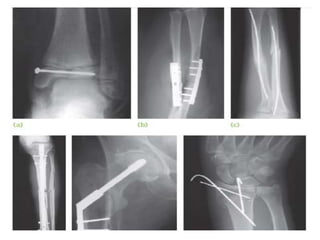

INTERNAL FIXATION

-Bone fragments may be fixed with screws, a

metal plate held by screws, a long intramedullary

rod or nail (with or without locking screws),

circumferential bands or a combination of these

methods.

-Properly applied, internal fixation holds a

fracture securely so that movement can begin at

once; with early movement the ‘fracture disease’

(stiffness and edema) is abolished.

Indications of internal fixation

1. Fractures that cannot be reduced except by

operation.

2. Fractures that are inherently unstable and prone

to re-displace after reduction (e.g. mid-shaft

fractures of the forearm and some displaced ankle

fractures).

- Also included are those avulsion fractures liable

to be pulled apart by muscle action (e.g. transverse

fracture of the patella or olecranon).

3. Fractures that unite poorly and slowly, principally

fractures of the femoral neck.

INTERNAL FIXATION -Bone fragmentsmay be fixed with screws, a metal plate held by screws, a long intramedullary rod or nail (with or without locking screws), circumferential bands or a combination of these methods. -Properly applied, internal fixation holds a fracture securely so that movement can begin at once; with early movement the ‘fracture disease’ (stiffness and edema) is abolished.

Indications of internalfixation 1. Fractures that cannot be reduced except by operation. 2. Fractures that are inherently unstable and prone to re-displace after reduction (e.g. mid-shaft fractures of the forearm and some displaced ankle fractures). - Also included are those avulsion fractures liable to be pulled apart by muscle action (e.g. transverse fracture of the patella or olecranon).

3. Fractures thatunite poorly and slowly, principally fractures of the femoral neck. 4. Pathological fractures in which bone disease may prevent healing. 5. Multiple fractures where early fixation (by either internal or external fixation) reduces the risk of general complications and late multisystem organ failure 6. Fractures in patients who present nursing difficulties (paraplegics, those with multiple injuries and the very elderly).